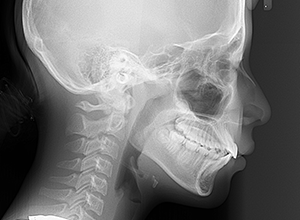

X-Ray

X-Ray所見

セファロ所見 SNAは84.3°、SNBは77.2°、ANBは7.1°とskeletal ClassⅡ、垂直的にはロウアングルの骨格形態をしていた。 上顎前歯は唇側傾斜を呈していた。

パノラマ所見 後継永久歯の歯数や萌出方向の異常は認められなかった。